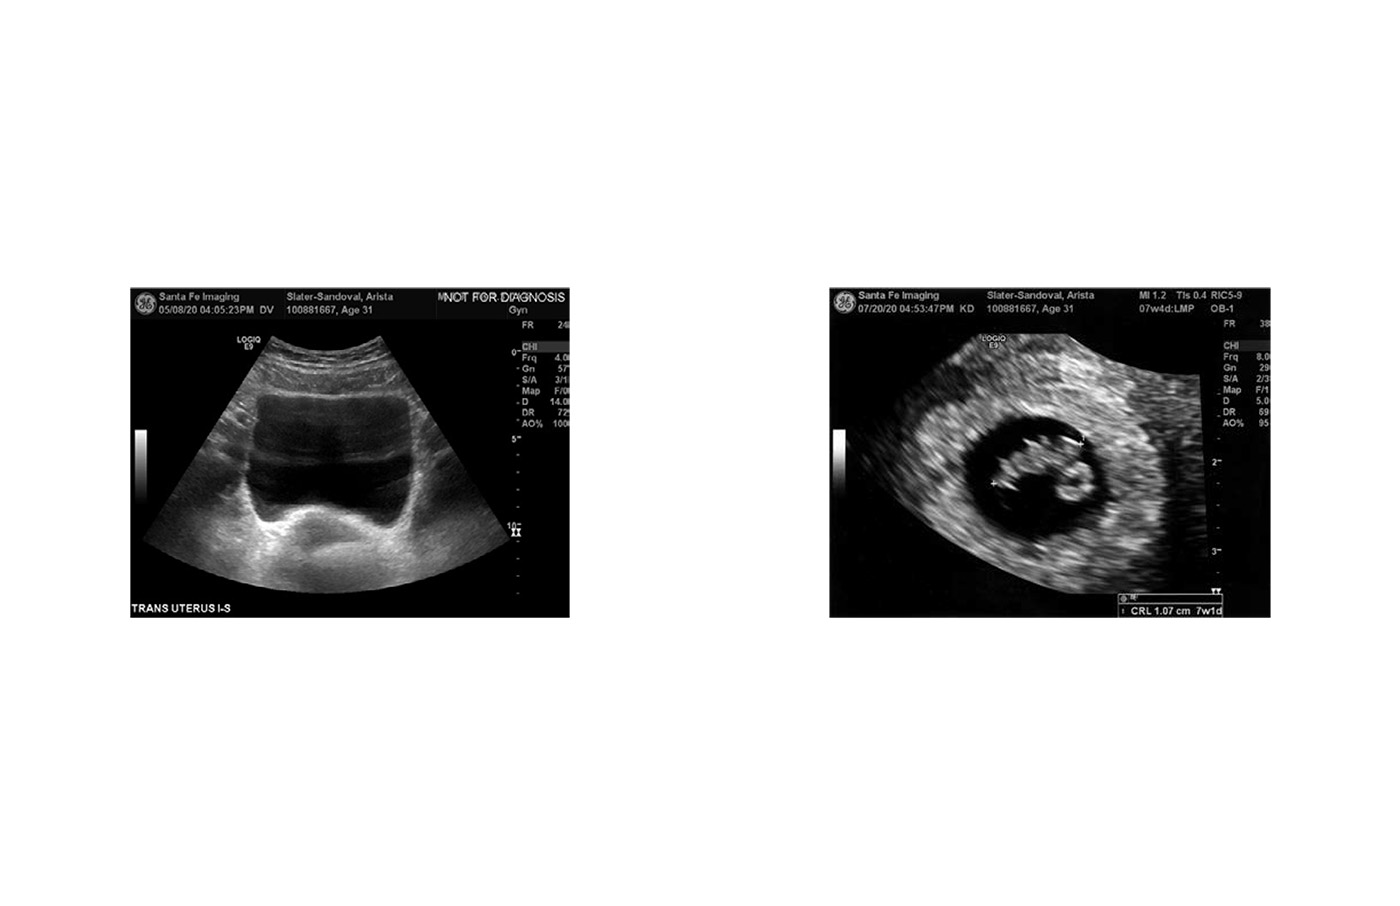

When referring to the female body a blighted ovum speaks to a type of miscarriage most often occurring within the first trimester. In clinical terms, an anembryonic pregnancy occurs when a fertilized egg attaches itself to the uterine wall, but the embryo does not develop to produce a viable life. A pregnancy sac forms and grows but not the embryo itself, no fetal pole (heartbeat) is produced. Now blighted, the womb is a barren land not fit to sustain life, a stark comparison first coined by male doctors in the mid 1800’s.

This book is a reminder of the hope for life, the physical reality for my body, and the lived experiences of grieving two consecutive miscarriages.